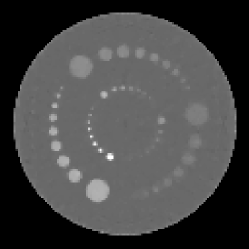

The CT configuration considered throughout this work is fan-beam, in which a source and detector pair rotate about a central field-of-view, acquiring discrete projection data at a fixed number of views. In particular, we consider a flat detector with uniform detector bin spacing as in Fig. 1.

The reconstruction algorithm used was the FBP algorithm discussed in section 2. Projection data for the reference case was acquired over a full rotation at 1024 evenly spaced angles with 256 detector elements. The reconstruction was performed onto a pixel image grid with pixels roughly twice the size of a single detector element. The images were then cropped to a central pixel ROI, which was then displayed at magnification. Black and white lines were then superimposed on the image in order to aid the observers in localizing the signal at the center of the ROI. The reference images for the human and model observer study were reconstructed without regularization, i.e. with only the ramp kernel used for filtration. The ratio of the source-to-detector distance to the source’s radius of rotation was . The reference reconstructed signal is shown on the top left of Fig. 1. Visible artifacts in the reconstructed signal are a result of the discretization in the sinogram and image domains and the small size of the signal. This small signal size is desirable in this case because we can then expect greater variability in observer performance with respect to the reconstruction algorithm with the given noise model. The corresponding Hotelling template is pictured on the top right of Fig. 1.